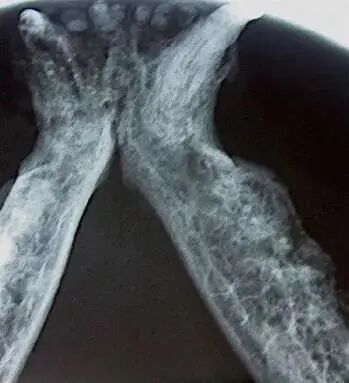

需要用更精准的诊断方式:拍摄专门的牙齿X光片

牙吸收病基于影像学分型——分为1型,2型,3型

牙吸收病的程度分级

1级

早期的牙吸收病变只影响牙骨质层而还未延伸到牙本质,病灶较小

牙吸收病变延伸至牙本质 ,但并无影响

2级

3级

牙吸收病影响到牙髓腔, 出现髓腔吸收

牙冠和牙根的病灶严重度相等

4级A型

牙根的病灶比牙冠严重

4级C型

5级

牙的残迹模糊只有牙的影子,牙龈已覆盖原来牙冠的位置